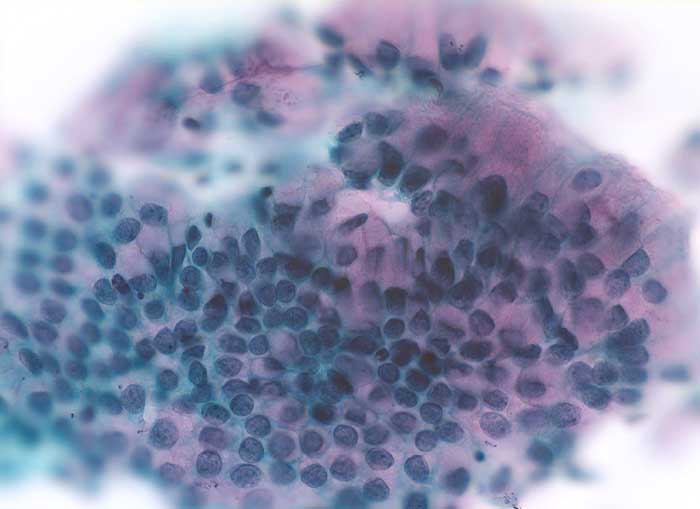

PathoPic ID 6101 - Zylinderepithelien

Zylinderepithelien

Normalbefund

Zervix

Genitalorgane, weiblich

Zervixabstrich: regelmässiger honigwabenartiger Zellverband ohne Atypien. Die Zylinderzellen enthalten reichlich rosafarbenen Schleim.

Jahreskontrolle

Zytologie

400